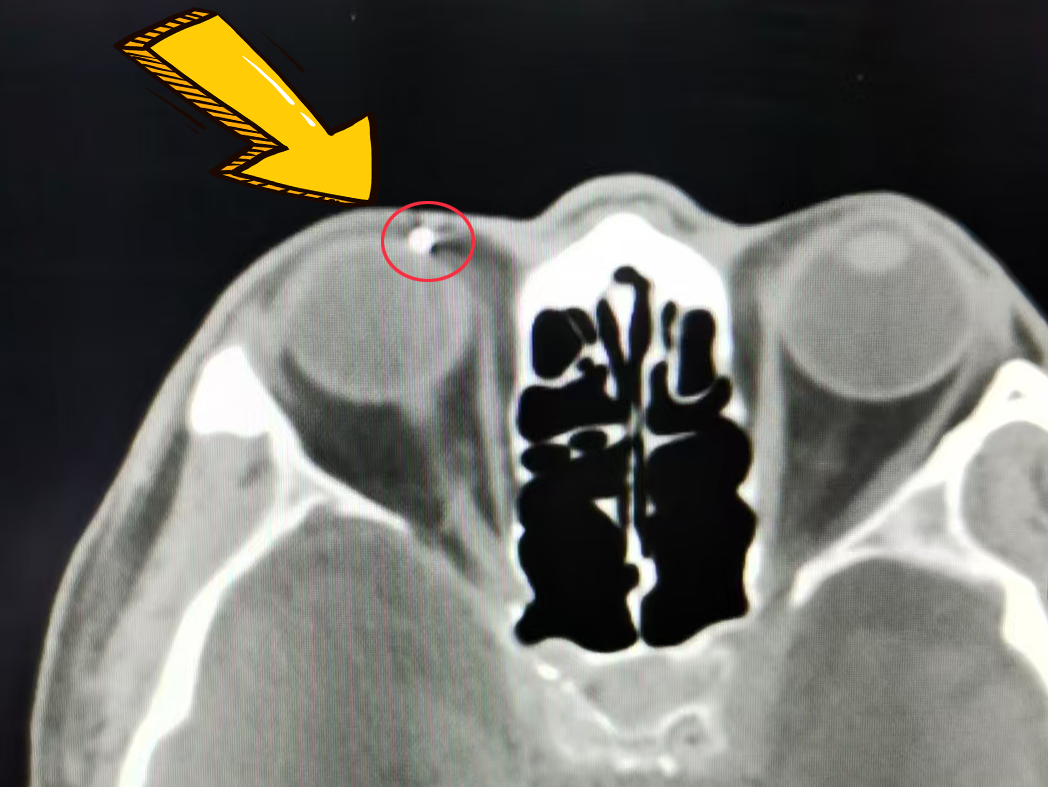

放射科医生在术前筛查时,敏锐察觉到其右眼眶内存在金属异物。考虑到磁共振检查可能对眼球造成二次伤害,医生紧急叫停检查,改为CT进一步确诊。

看着 CT 影像上清晰的高亮点,赵先生满心困惑又焦虑:“年轻时在造船厂工作过,但要是受过伤肯定记得,这异物藏了这么多年,以后做磁共振岂不是都受影响?”这个突如其来的“眼中钉”,成了压在老人心头的一块心病。

放射科曹俊涛医生接过“定位接力棒”:CT 擅长显示异物与周围组织的毗邻关系,X光片则能精准锁定空间位置。通过头颅正位片+右侧位片的联合检查,他不仅进一步确认了异物位于右眼两点钟方向,更精准测算出异物大小及与眼眶的距离,为手术提供了基础坐标。